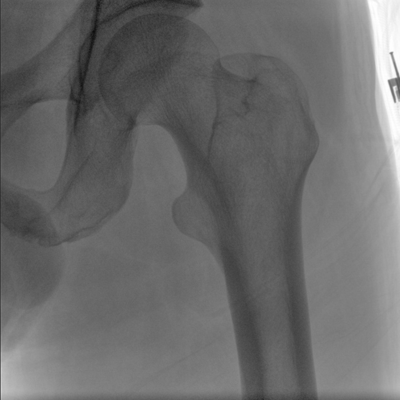

大尺寸動態(tài)平板探測器,高DQE、低噪聲、圖像清晰。采用多分辨率圖像增強處理技術(shù),不同部位不同圖像處理算法,滿足客戶多樣化的需求。

采用智能變頻脈沖透視技術(shù),優(yōu)化圖像質(zhì)量的同時降低輻射劑量,呵護醫(yī)患健康